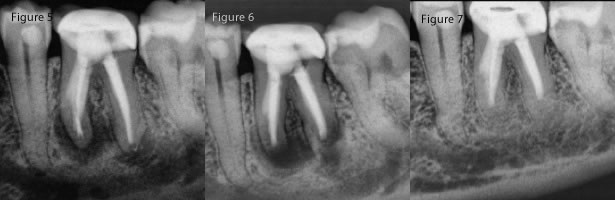

Category A and B would be defined as very good periodontal support with normal sulcular depths and buccal plate intact. Category A has no apical lesion and Category B and an apical lesion. The image below would show the surgical appearance once the tissue has been flapped.

Category A and B

Surgical View

Category C has normal sulcular depth and buccal plate intact, but the apical lesion extends about half way up the root.

Category D has an apical lesion, but in this case the buccal bone starts to become compromised and the sulcular depth extends well onto the root surface.

Category C and D

Category E is a condition where the apical pathology and the periodontal sulcus depth do join in a true combination periodontal/endodontic infection. The image below also shows the surgical view once the tissue has been flapped back.

Category E

Surgical View of a Category E

Category F is of course the worst periodontal condition for a tooth with no buccal bone at all and total attachment loss to the apex of the root. You can again see the image showing this surgical view with a total lack of buccal plate.

Category F

Surgical View of a Category F

It should be clear that category A, B will lead to the best chances for a surgical success. I also feel that category C conditions lead to predictable outcomes as well. The drop off in success really occurs most steeply at category D and the final categories of E and F should essentially be avoided entirely.